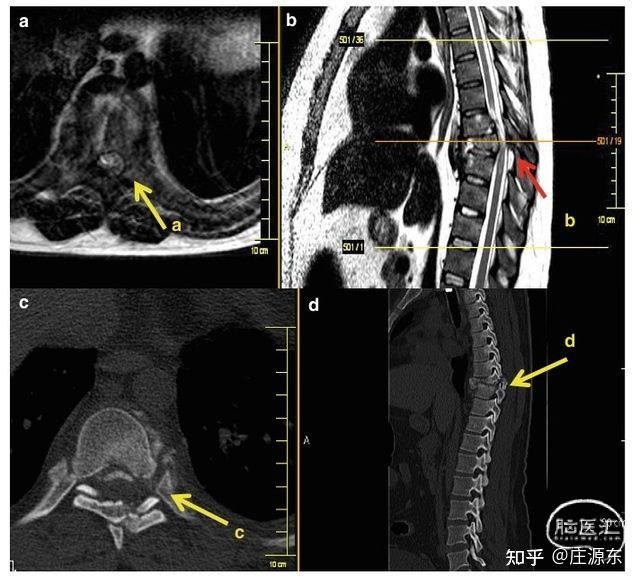

为目前已知的最好的建立临床 - 影像学相关性的方法,对于急性脊髓创伤术前的入路计划和提高疗效至关重要(图 1,图 2)。

图 1 同一病例 MRI(a,b)和 CT(c,d)在诊断骨和脊髓损伤方面的比较。a. T1 加权轴位片示椎管狭窄和脊髓受压;b. T2 加权矢状位提示椎管压迫及脊髓挫伤。 c. CT 轴位片示后方结构骨折,但未见压迫。d. 矢状位示胸椎脱位,后方结构骨折。